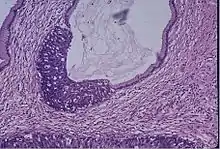

Microscope image of the cervical gland showing an area of high grade epithelial dysplasia.

Cervical screening by the Pap test or other methods is highly effective at detecting and preventing cervical cancer, although there is a serious risk of overtreatment in young women up to the age of 20 or beyond, who are prone to have many abnormal cells which clear up naturally.[24] There is a considerable range in the recommended age at which to begin screening around the world. According to the 2010 European guidelines for cervical cancer screening, the age at which to commence screening ranges between 20–30 years of age, "but preferentially not before age 25 or 30 years", depending on the burden of the disease in the population and the available resources.[25]